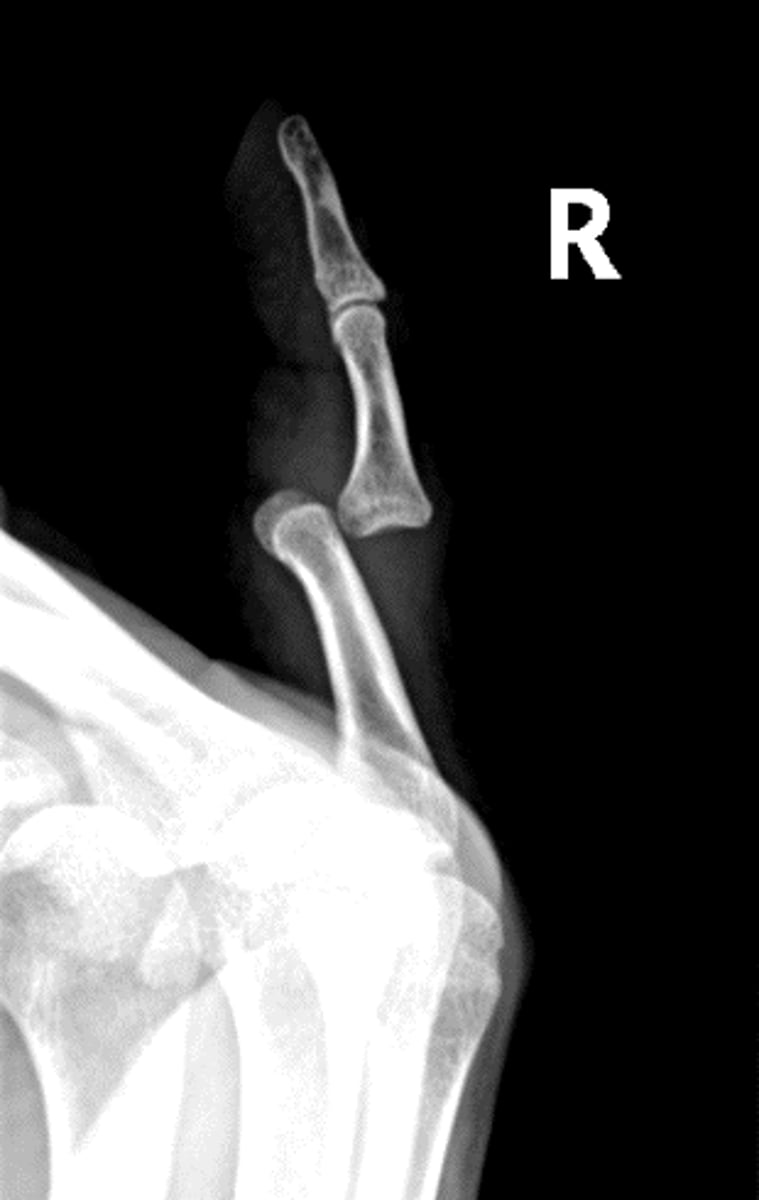

Lateral Elbow

Axial lateromedial for coronoid process elbow

Axial lateromedial for radial head elbow

Dislocation